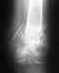

Re: Закрытый перелом пяточной кости

Эти вопросы уместно задать тому врачу, который видел рентгенограммы и принимал решения о выборе лечения. Переломы по форме разные, и нагрузка при каких-то безопасна раньше, при каких-то позже.